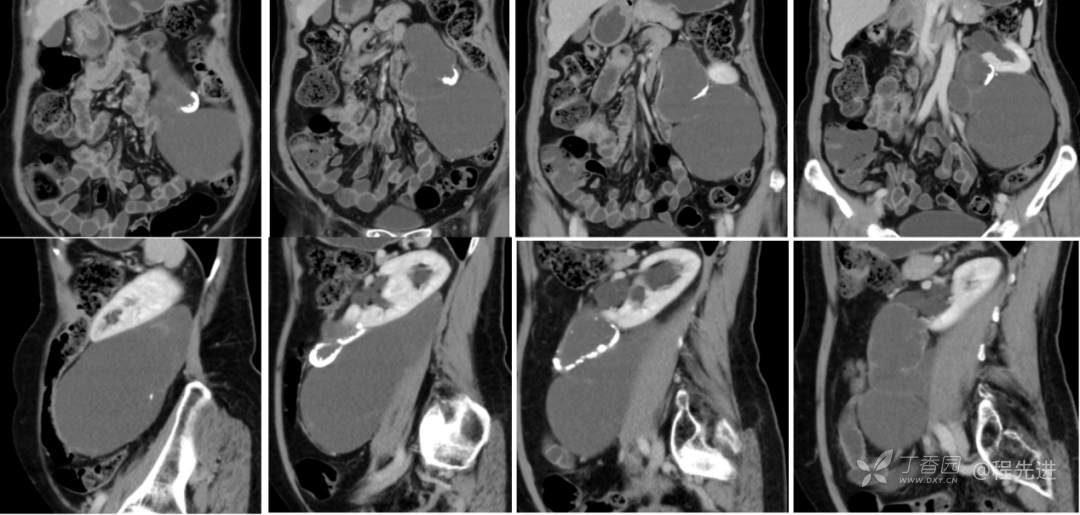

冠矢状位重建: